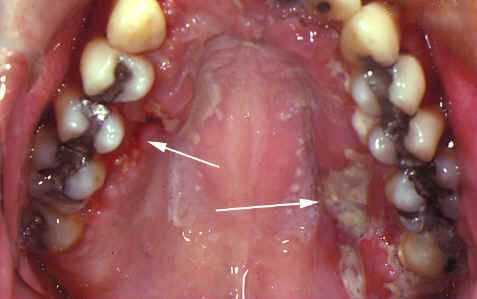

Участки кандидоза наблюдаются на щечной и нёбной слизистой оболочки рта, языке и обрабатываются антимикотическими средствами.

Герпетиформные язвы встречаются в виде гроздей изъязвленных дефектов на нёбе, но они возникают редко. Их этиология остается неизвестной, однако эмоциональные стрессы, травмы и нехватка пищевых компоненетов играют роль в патологическом процессе. Язвы полости рта связаны с мальабсорбцией. Персистирующие и не реагирующие на лечение язвы часто иссекают для исключения рака полости рта.